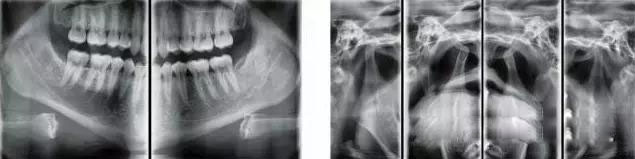

MSQJ2000-I口腔全景X射線機

產(chǎn)品簡介:

使用了50kHz高頻直流發(fā)生器,進(jìn)口齒科專用X射線管、手動式升降、電磁鎖定等,使其拍片時焦點小,圖像清晰,同時使X射線的輸出更加穩(wěn)定和準(zhǔn)確,從而減少了散射線對病人和操作人員不必要的輻射。并引進(jìn)日本先進(jìn)的scara投照平臺技術(shù)與工藝,使全景投照模式得以極大的拓展。豐富的投照程序選擇,為臨床診斷提供多種、實用的頜面影像信息。先進(jìn)的頜骨體層(全景)掃描技術(shù)方案使掃描聚焦與頜骨達(dá)到最佳彌合。直接成像影像還源性、清晰度均達(dá)到極高水平。

★ 體層掃描聚焦帶對頜骨前、后牙區(qū)域能夠完美地覆蓋

從而有效地減少無關(guān)組織對影像的干擾。在全部體層掃描過程中放大率恒定,影像不產(chǎn)生局部畸形。

★ 可增加多種投照焦點軌跡及十三種常用攝影模式

根據(jù)患者頜形大、中、小及平鈍、標(biāo)準(zhǔn)、尖窄(LN、S)的具體情況,可做多個適應(yīng)性(引型)調(diào)節(jié)。

★  除了口腔全景影像,還能拍攝頭顱正、側(cè)位影像、四均分的顎關(guān)節(jié)共四種影像。

拍攝顎關(guān)節(jié)時,只要在取出牙托架和咬合桿后,本機功能即自動切換,即可對左右顎關(guān)節(jié)(開口、閉口)拍攝,具有均衡的放大率,可獲得一張四均分的顎關(guān)節(jié)X射線影像。

頭顱:1.1倍    全景1.25倍   (恒定)